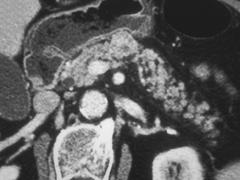

选项 A、典型症状是清晨自发性低血糖 B、是胰腺内分泌肿瘤中最常见的 C、绝大多数是恶性肿瘤 D、单发肿瘤占90%以上 E、给予葡萄糖或进餐后症状缓解

答案 C